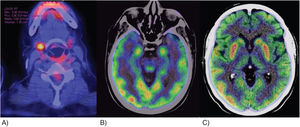

Clinical observationCase 1: A 68-year-old female patient began with loss of alertness, disorientation, delusions, visual hallucinations, and tonic-clonic seizures. The brain MRI identified lesions in the frontal lobes with punctate and hyperintense characteristics in T2 and flair sequences, as well as decreased frontal cortical brain volume. During her hospital stay, she presented gelastic crises, for which an electroencephalogram was performed which reported: abnormal stroke with diffuse dysfunction, ictal characteristics, electrical onset, recruiting rhythm in the delta range followed by tip activity in bilateral posterior regions, with right predominance, for which treatment with levetiracetam was initiated and anti-Smith, anti-SS-A and anti-SS-B negative antibodies were determined. Total positive ANA was 1:640, with a dense, fine, mottled pattern. PET-CT was performed as a supplement to the approach, in which generalised cerebral hypometabolism was reported, as well as increased basal ganglia uptake (Fig. 1A). Salivary glandular biopsy was performed with a report of atrophy of mucinous acini with a focus of moderate lymphoid infiltrate of more than 50 lymphocytes, as well as data on fibrosis, ductal ectasia and abundant apoptotic bodies (Fig. 2). Management was started with boluses of methylprednisolone and later rituximab, presenting clinical improvement.

(A) Positron emission tomography (PET-CT) of case 1. Changes in salivary gland density were observed that correlate with Sjögren's disease, with an increased metabolism focus in the right submandibular gland of 10 mm with a SUVmax of 5.8. B and C) PET-CT for case 2. Increased metabolism was observed in both hippocampi, the right temporal cortex and both putamens. The rest of the cortex was observed to have generalised hypometabolism.

Case 2: A 20-year-old female patient with no previous comorbidities, who presented with sudden disorganised thinking, poor speech content, delirium of persecution, auditory hallucinations and disorientation, as well as catatonic syndrome, characterised by hypomimia, mutism, anergy and apathy. She presented a suicide attempt with a high degree of lethality, with subsequent pharmacological management by Psychiatry. A PET-CT scan was performed, which documented a lateral occipital cortex with decreased metabolism, caudate nuclei and putamen with metabolic increase, as well as cerebellum with generalised hypometabolism (Fig. 1B and C). Autoimmune encephalitis antibodies were negative. Total ANA with titration was 1:320 with a dense fine mottled pattern, anti-DNA DS recorded 34.5 IU/ml, anti-SS-A: 153.6 IU/ml and anti-SS-B negative. Treatment with methylprednisolone boluses was initiated. Four months after her discharge, she presented akinetic mutism, inability to perform daily activities and discoordination, for which plasmapheresis was performed, with improvement in the condition.